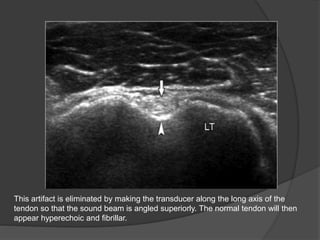

This artifact is eliminated by making the transducer along the long axis of the

tendon so that the sound beam is angled superiorly. The normal tendon will then

appear hyperechoic and fibrillar.